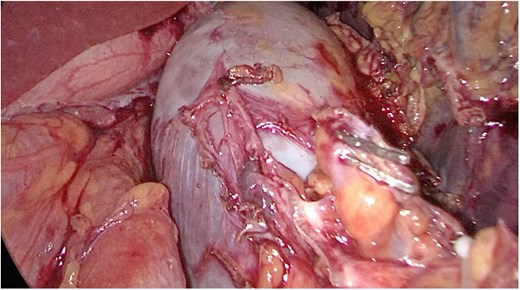

Multidisciplinary discussion was held to evaluate the most appropriate course of action for the patent condition, and the consensus was reached to pursue embolization as a first intervention. Embolization was performed by interventional radiology with no complications post-procedure, and the patient was optimized prior to her procedure. Patient was taken to the operating room in stable conditions. The spleen was enlarged around 20 cm. Inferiorly, the omentum and part of the transverse colon was attached to the spleen (Fig. 3), so we freed the omentum from the splenic tissue. The dissection continued until reaching short gastric vessels and entering the lesser sac (Fig. 4). Once the lesser sac was entered, the splenic vessels were identified (Figs 5 and 6), the splenic vein was hugely dilated with multiple collateral branching vessels at the hilum. Gaining posterior mobilization of the vein was challenging. The splenic artery was tortuous from the insertion around itself (Fig. 7). After complete mobilization of the fundus, we elected to divide each vessel starting with the splenic artery so we can achieve full mobilization of the vein (Fig. 9). After controlling the splenic artery, the splenic vein was dissected proximal to the splenic hilum (Fig. 8). It was hugely dilated and its wall is thickened secondary to AV fistula. It was difficult to achieve circumferential dissection, so we decided at that moment to convert to laparotomy to complete ligating the vein and to retrieve the specimen (Fig. 10a and b).

Anterior portion of the splenic vein seen posterior to the stomach.

Splenic vein mobilized from the side. Clips seen on branches of the vein.